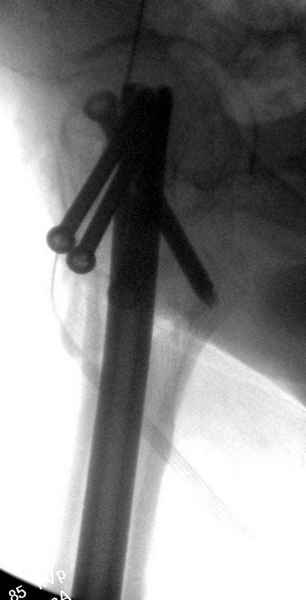

Профилактику дальнейшего раскола неполного перелома шейки провели тремя канюлированными шурупами.

На второй день после выписки упал дома. Снимки приложены. Коллеги рекомендуют удаление шурупа и вытяжение. Что делать?

Привет из солнечного Будапешта с Eurotrauma-2008. Да, замечательный пример. Получается, профилактику расхождения отломков шейки надо было проводить каким-то реконструкционным или проксимальным гвоздем, причем сразу длинной версией. Сейчас, наверно, так и надо бы сделать.

Убрать винты, каким-то джойстиком в вертельной области сделать репозицию шейки, фиксировать ее спицами, а дальше вправлять и фиксировать как вертельный перелом.

Решайте проблемы по мере поступления. На первом этапе решение одно, и на мой взгляд верное. Ситуация изменилась кардинально - другое решение. Я бы избрал ресинтез, убрав винты заменил на Гамму. Что с ним будет послезавтра? - Будем решать послезавтра. Такая наша доля.

Правильно, ситуация изменилась, как говорят у нас теперь "different animal", надо решать проблему подвертельного перелома. При наличии различных вариантов фиксаторов, включая Страйкер Гамма 3, мы выбрали DePuy Antegrade Trachanteric Nail из-за многовариантности проксимальной фиксации и двойного изгиба. Вводится через вертел под 8 градусным углом, и есть достаточный передний диафизарный изгиб, предупреждающий пенетрацию дистального переднего кортекса.

Кто знает что дальше, мысленно готовы к проксимальной артропластике.